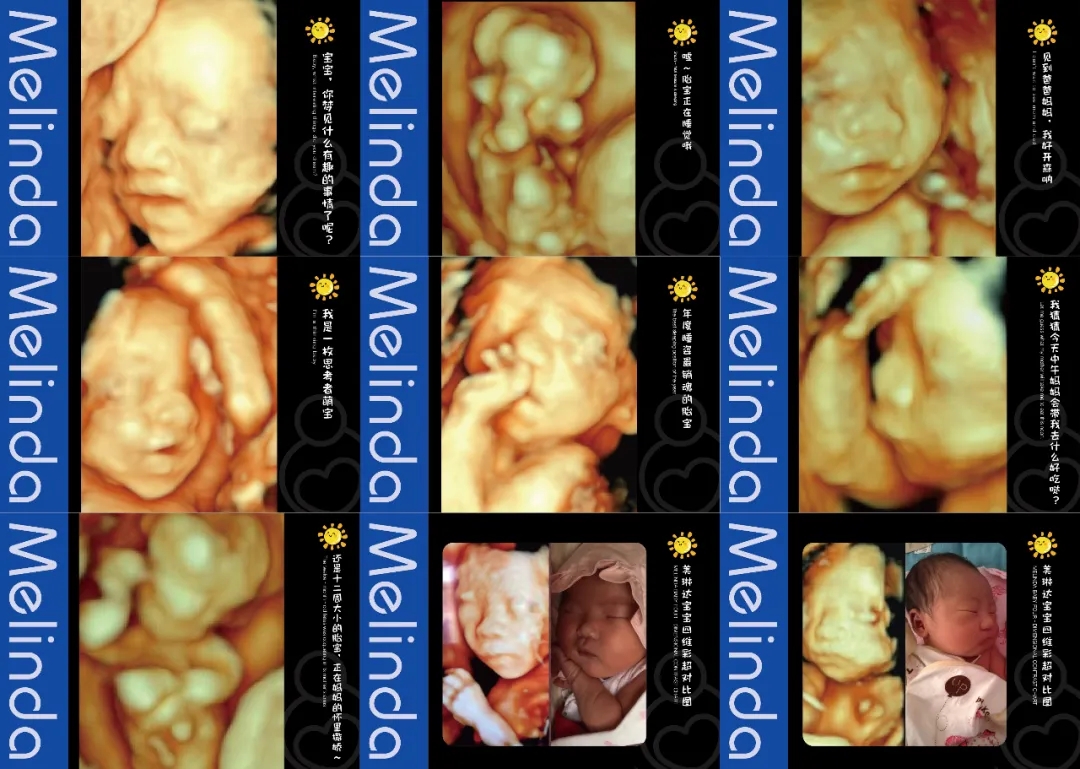

(美琳达四维宝宝照片)

大屏幕同时播放宫内情况(躺床上可以清晰的看到胎宝情况)检查床旁放置舒适纯皮沙发,支持家属陪伴检查。重要的是,美琳达也会提供胎儿写真照片,留作纪念。

美琳达超声科引进多台美国GE-E10、美国GE-E8等系列机器。能够提高细节分辨率,满足从早孕期研究到复杂胎心的全程早期检查和诊断,清晰并动态记录宝宝在子宫内的活动和成长历程。